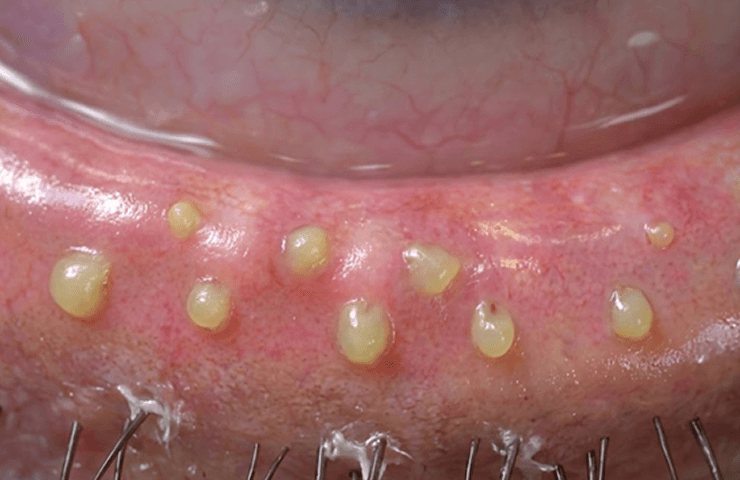

1Precision Extraction of Blocked Oil Glands

When the meibomian gland openings inside the eyelid become blocked with hardened oil residue, inflammation and dryness worsen.

Squeezing involves skilled medical professionals using specialized instruments to open blocked openings

and directly extract deteriorated oils to promote healthy gland circulation.

Why is squeezing necessary?

Meibomian glands consist of very fine channels.

Once these channels become blocked with hardened oil (sebum),

even the best eye drops become less effective.

Squeezing physically removes stagnant debris from inside the eyelids,

much like extracting a clogged pore at a dermatology clinic,

allowing the oil glands to breathe again an essential process.